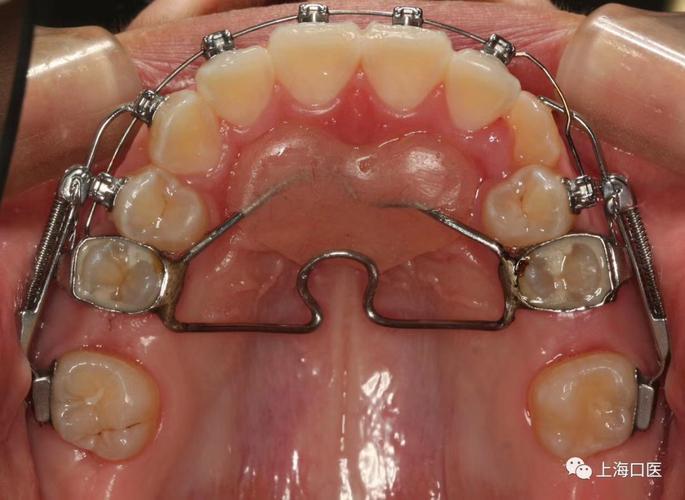

磨牙后推的矫治装置多样,根据作用方式可分为机械力装置与磁力装置两大类,各有特点与适用场景,为更直观理解,以下通过表格对比常见装置的类型、原理、优缺点及适用情况:

临床操作流程通常分为四个阶段:术前评估与方案设计、装置粘接与加力、移动过程中的监控、保持与稳定,术前评估需通过X线片(全景片、头颅侧位片)、口内模型、口扫数据等分析牙列拥挤程度、磨牙位置、牙根形态及骨量;方案设计需确定移动目标(如需创造的间隙量)、选择合适的支抗类型(如种植钉、腭部支抗装置)及矫治装置,装置粘接时,需彻底清洁牙面,精确定位托槽或附件位置,确保施力方向与磨牙长轴平行(避免倾斜),加力后患者需每4-6周复诊,通过临床检查、X线片评估移动效果(如磨牙是否整体远中移动、有无支抗丧失),必要时调整力值或装置,当磨牙达到目标位置(通常为第一磨牙牙尖距离第二前磨牙牙尖远中约1-2mm)后,需保持6-12个月,期间可使用 Hawley 保持器或固定保持器维持效果,防止复发。